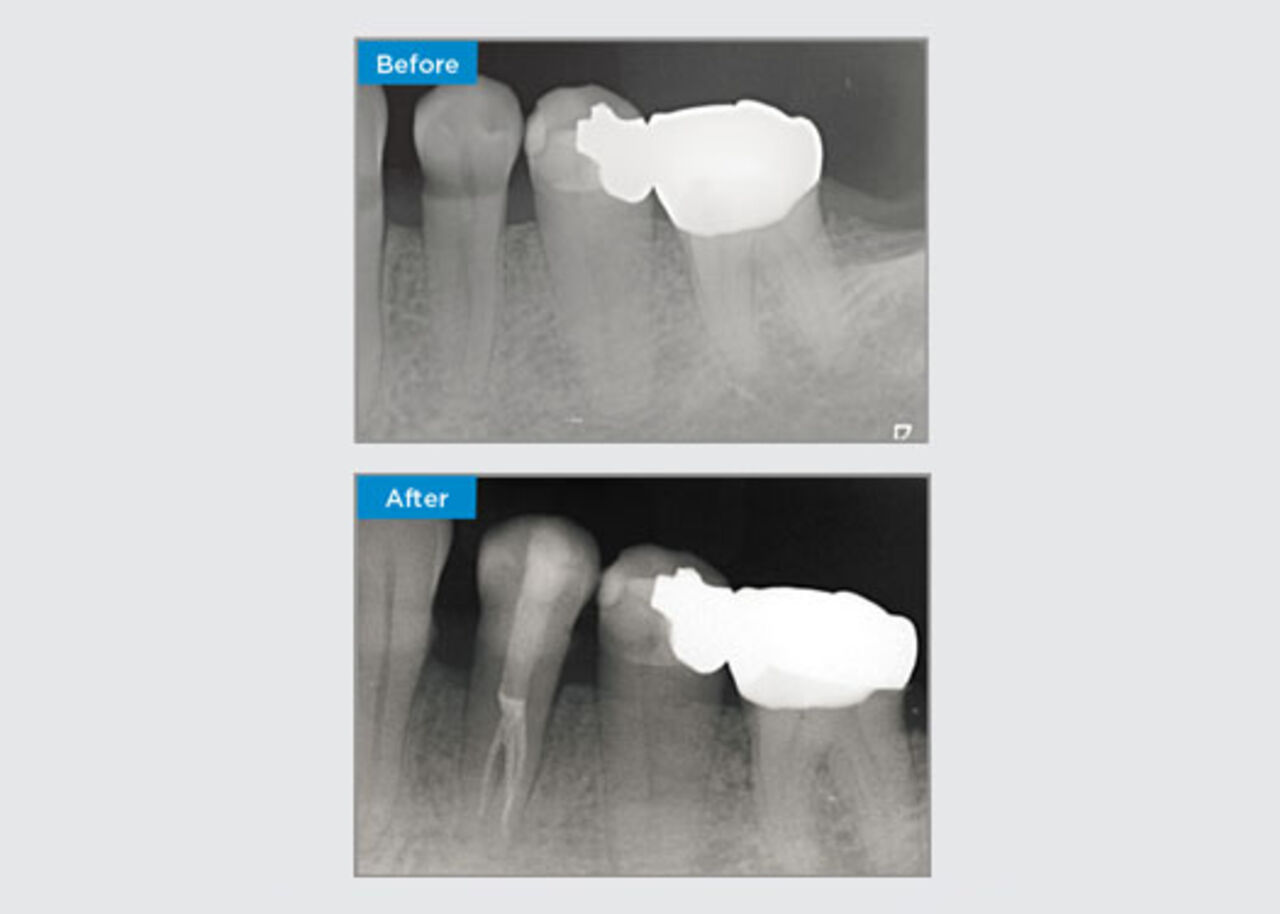

Clinical Cases

Clinicians far and wide, throughout Australia and New Zealand kindly share relevant, interesting and sometimes challenging patient presentations, along with their selection of materials and methods to optimise their patients' outcomes.